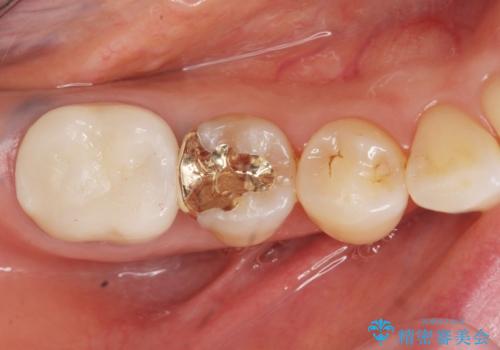

咬合力が強いため、割れる心配がなく強度の高いPGA(ゴールド)インレーをご希望されました。

治療後はしみなくなり、違和感のない自然な咬み心地にご満足頂けました。

「割れる心配のないゴールドにしたいけれど、目立ってしまうかしら...」と心配されており、不要に歯質を削合しないよう注意を払い最小限の大きさのインレーを装着したところ、「あまり目立たなくて良かった!」とおっしゃって下さいました。